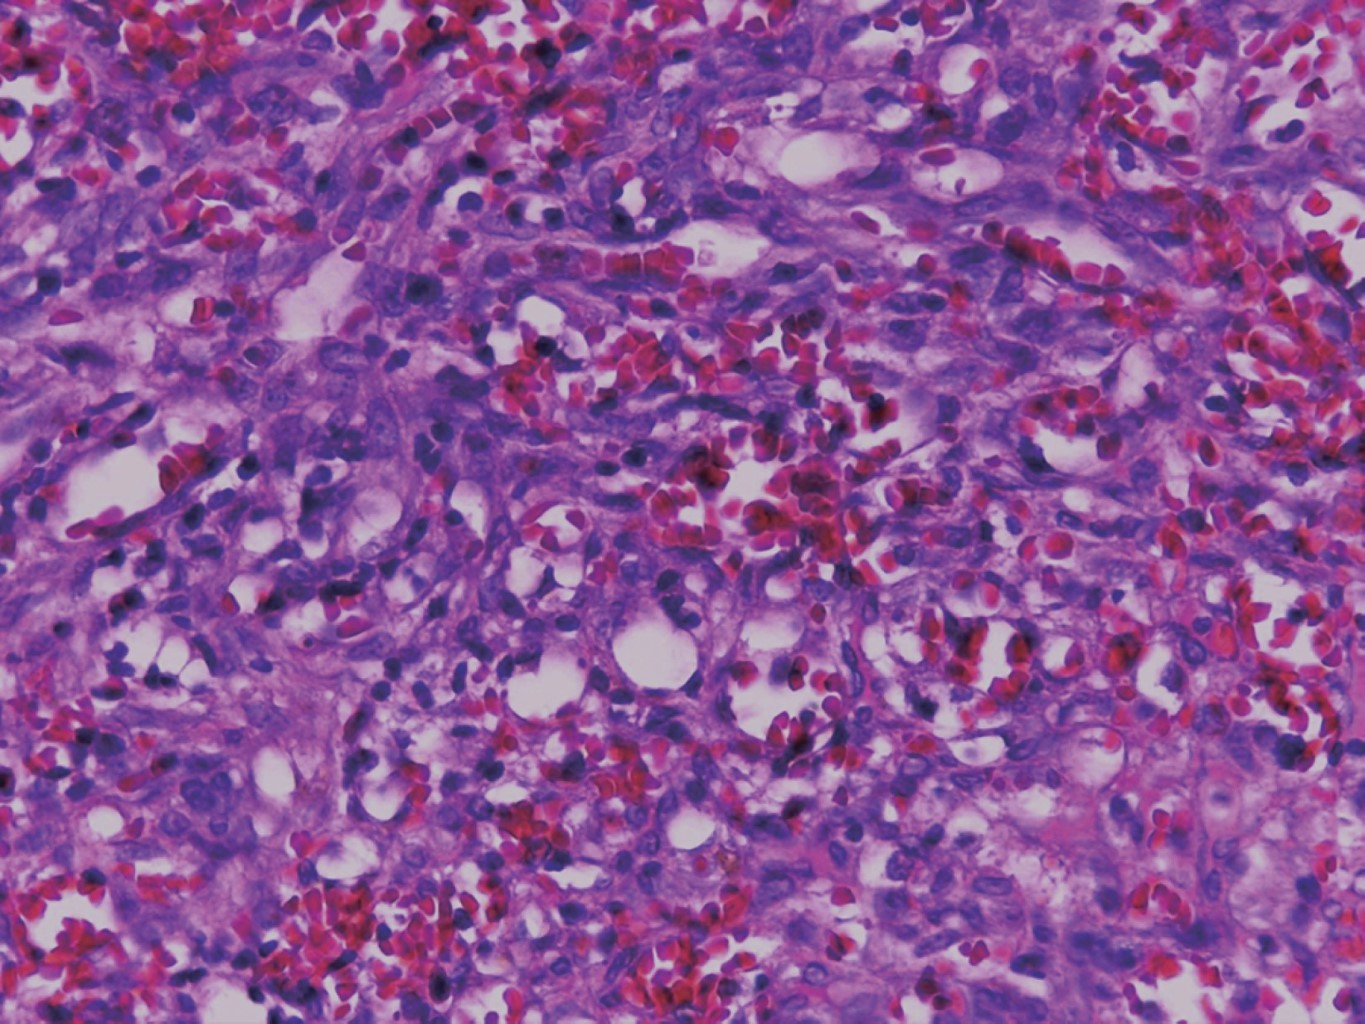

El tratamiento fue mediante escisión por rasurado y electrocauterización (Figura 4). En el estudio histológico se observó una neoformación exofítica cuya epidermis presenta hiperqueratosis paraqueratósica focal, atrofia y zonas ulceradas. En el espesor de la dermis se observan numerosos vasos neoformados dilatados y congestionados cuya pared se encontró formada por una sola hilera de células endoteliales, los cuales se entremezclan con numerosas células fusiformes que siguen diversos trayectos inmersos en un estroma edematoso (Figuras 5, 6 y 7).

El diagnóstico es clínico, pero es necesario confirmarlo por estudio histopatológico en el cual se observan células fusiformes, proliferación de vasos irregulares con hendiduras vasculares, extravasación de hematíes, e infiltrado leucoplasmocitario y glóbulos hialinos intra y extracelulares, así como el característico signo del promontorio. La PCR y la inmunohistoquímica para la detección del antígeno nuclear asociado a latencia (LANA-1) del virus VHH-8 son positivos.9

Figura 5

Figura 6

Figura 7